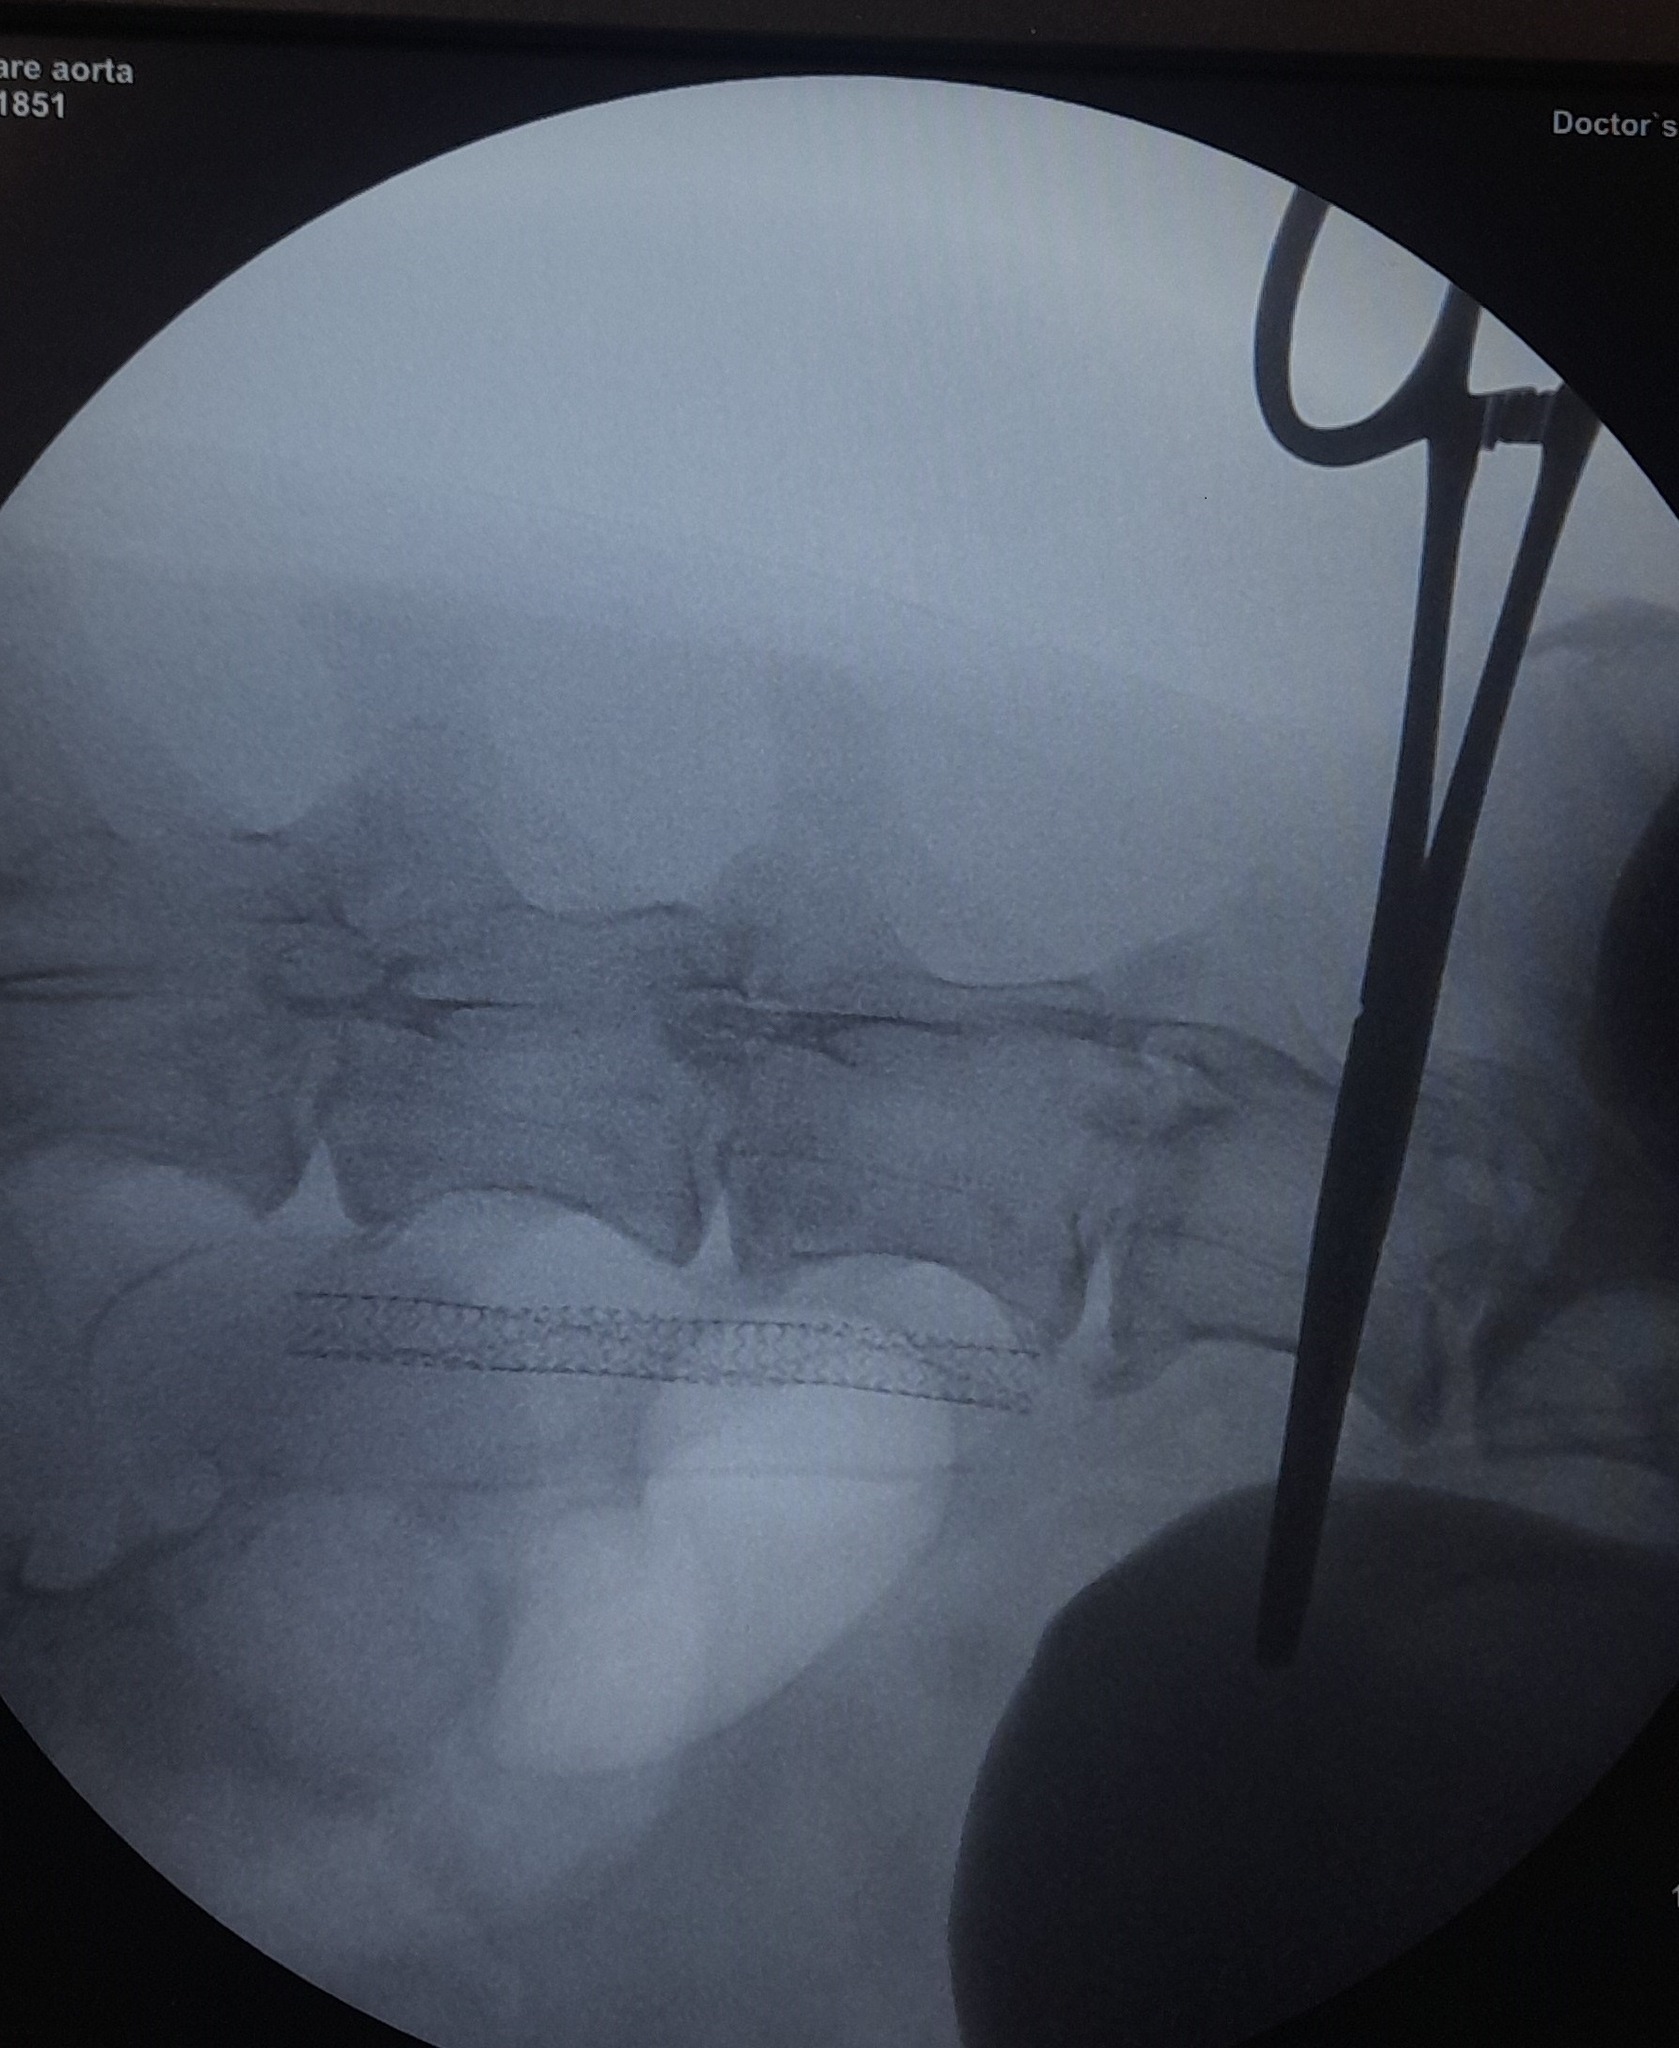

După 14 zile de la implantarea în premieră ABSOLUTĂ în România, şi probabil europeană/mondială, efectuată de către echipa Română de Cardiologie Intervenţională AvantGuarde CardioTeam Bucureşti (echipă formată şi dezvoltată ca etalon de performanţă ştiinţifică, dar totodată şi reprezentant pe plan internaţional recunoscut al Şcolii de Medicină Veterinară din România) a unui stent la nivelul arterei Aorte Infrarenale la un câine de 16 ani suferind de Boală Ocluzivă Ateromatoasă (afecţiune extrem de rar descrisă în literatura de specialitate, actual fiind descrise doar cazurile de stentare în tromboză sau în anevrism aortic de către Kelly Gavin, Chick Weisse, Allyson Berent, Sigal Klainbart, etc., nu şi în cazul plăcilor ateromatoase) cu deficit locomotor sever pe trenul posterior, secundar reducerii dramatice a fluxului de sânge (ca urmare a stenozării severe aortice). Pacientul nostru şi-a recăpătat funcţia locomotorie în proporţie de 80% la două săptămâni postoperator.

Din cauza dimensiunii foarte mici a arterei femurale la câine (comparativ cu omul) această procedură este mult mai complicată celor efectuate în medicina umană. Un caz similar operat cu succes anul trecut tot de echipa noastră de medici exclusiv veterinari pe un pacient de 6 kg (prin abordarea arterei femurale care avea un diametru de 2.3 mm), evaluat iniţial la o altă universitate din ţară, este comparabil poate doar cu operaţiile efectuate în Chirurgia Cardiacă Intervenţională Pediatrică.